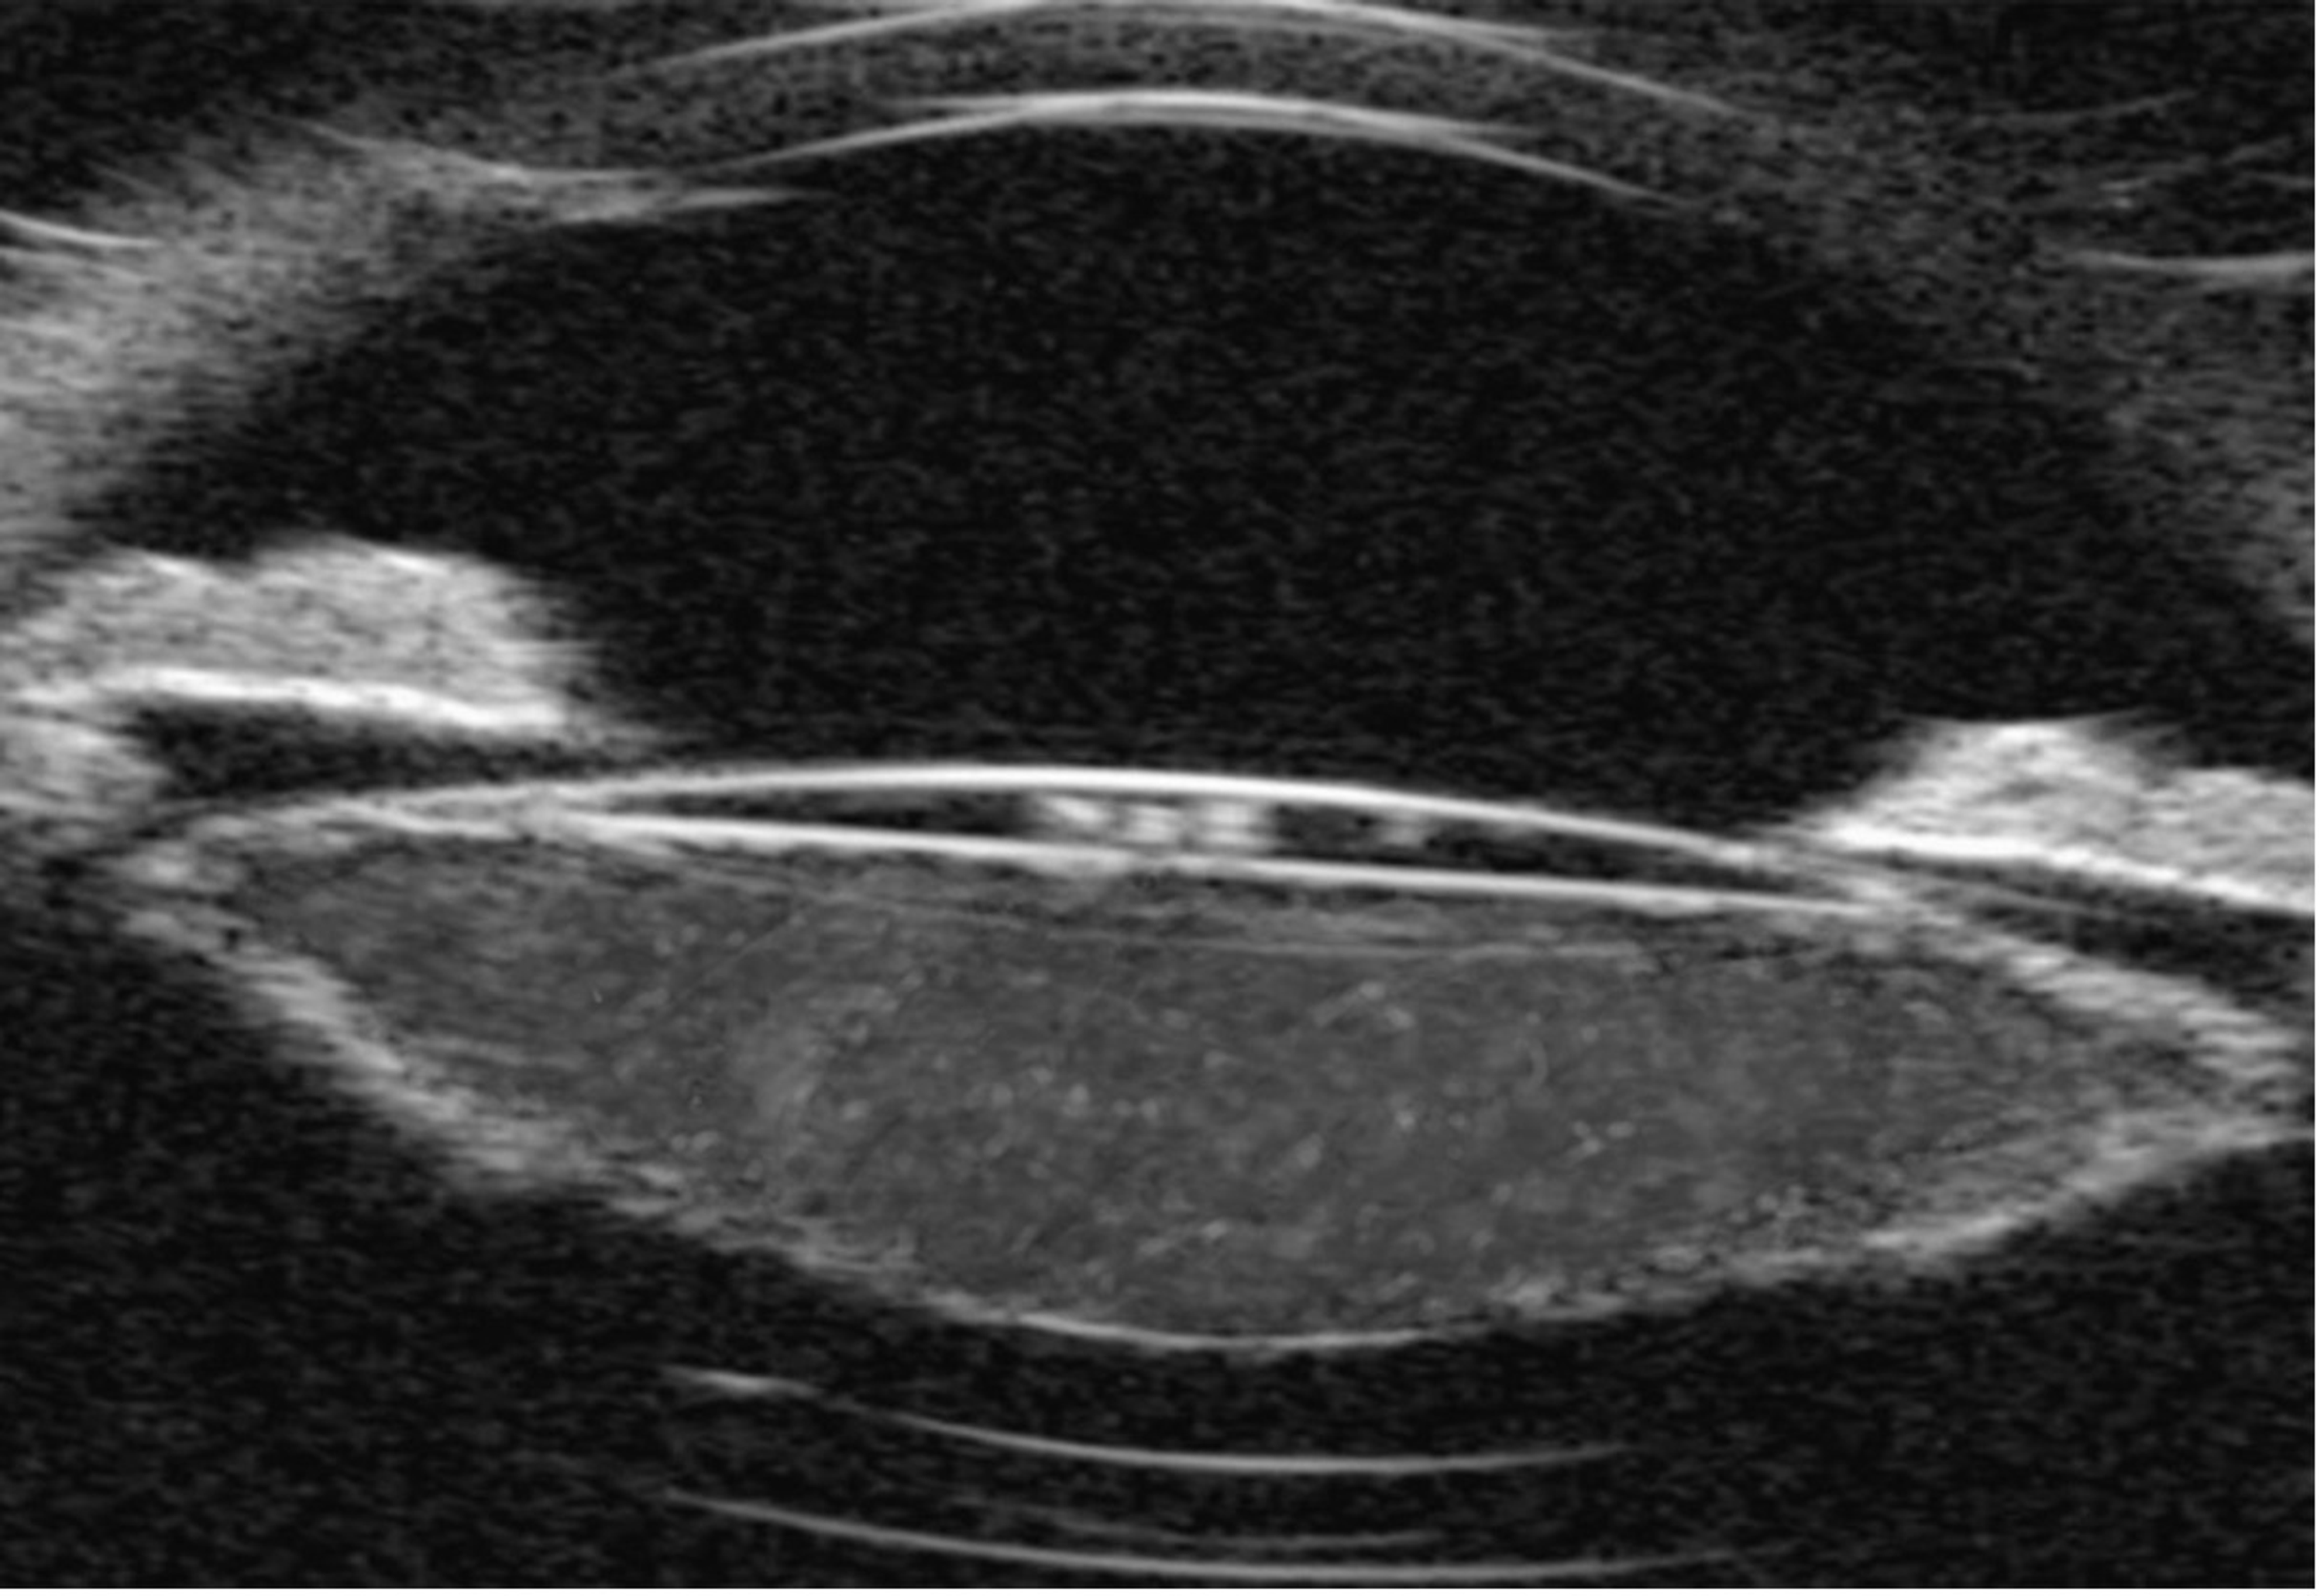

Wrinkled and fibrotic lens capsule Cataract Coach Lens Capsule Wrinkled the main cause of posterior capsule wrinkle is the contraction of the capsule surrounding the implanted lens. the wrinkled anterior lens capsule. Area of zonular absence seen between cataract and iris. yes, a wrinkle in the lens after cataract surgery can be corrected through a procedure called yag laser capsulotomy. a yag laser posterior capsulotomy is. Lens Capsule Wrinkled.